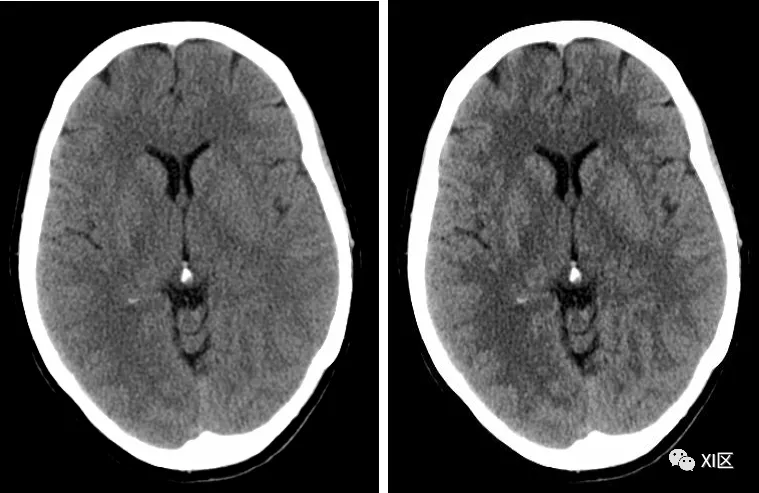

神经最佳对比度旨在提高低对比度分辨率,同时保持噪声不受影响,即提高对比度噪声比,有利于提高图像质量和组织分化或减少辐射剂量。

不使用(左)和使用(右)神经最佳对比技术获得的图像对比。

神经最佳对比在特定卷积核中生效,使用带有神经最佳对比技术的特定卷积核即可。H21,H31,H41以及Hr32,Hr36,Hr40,Hr44的卷积核均有此技术,可以比较一下试试看。